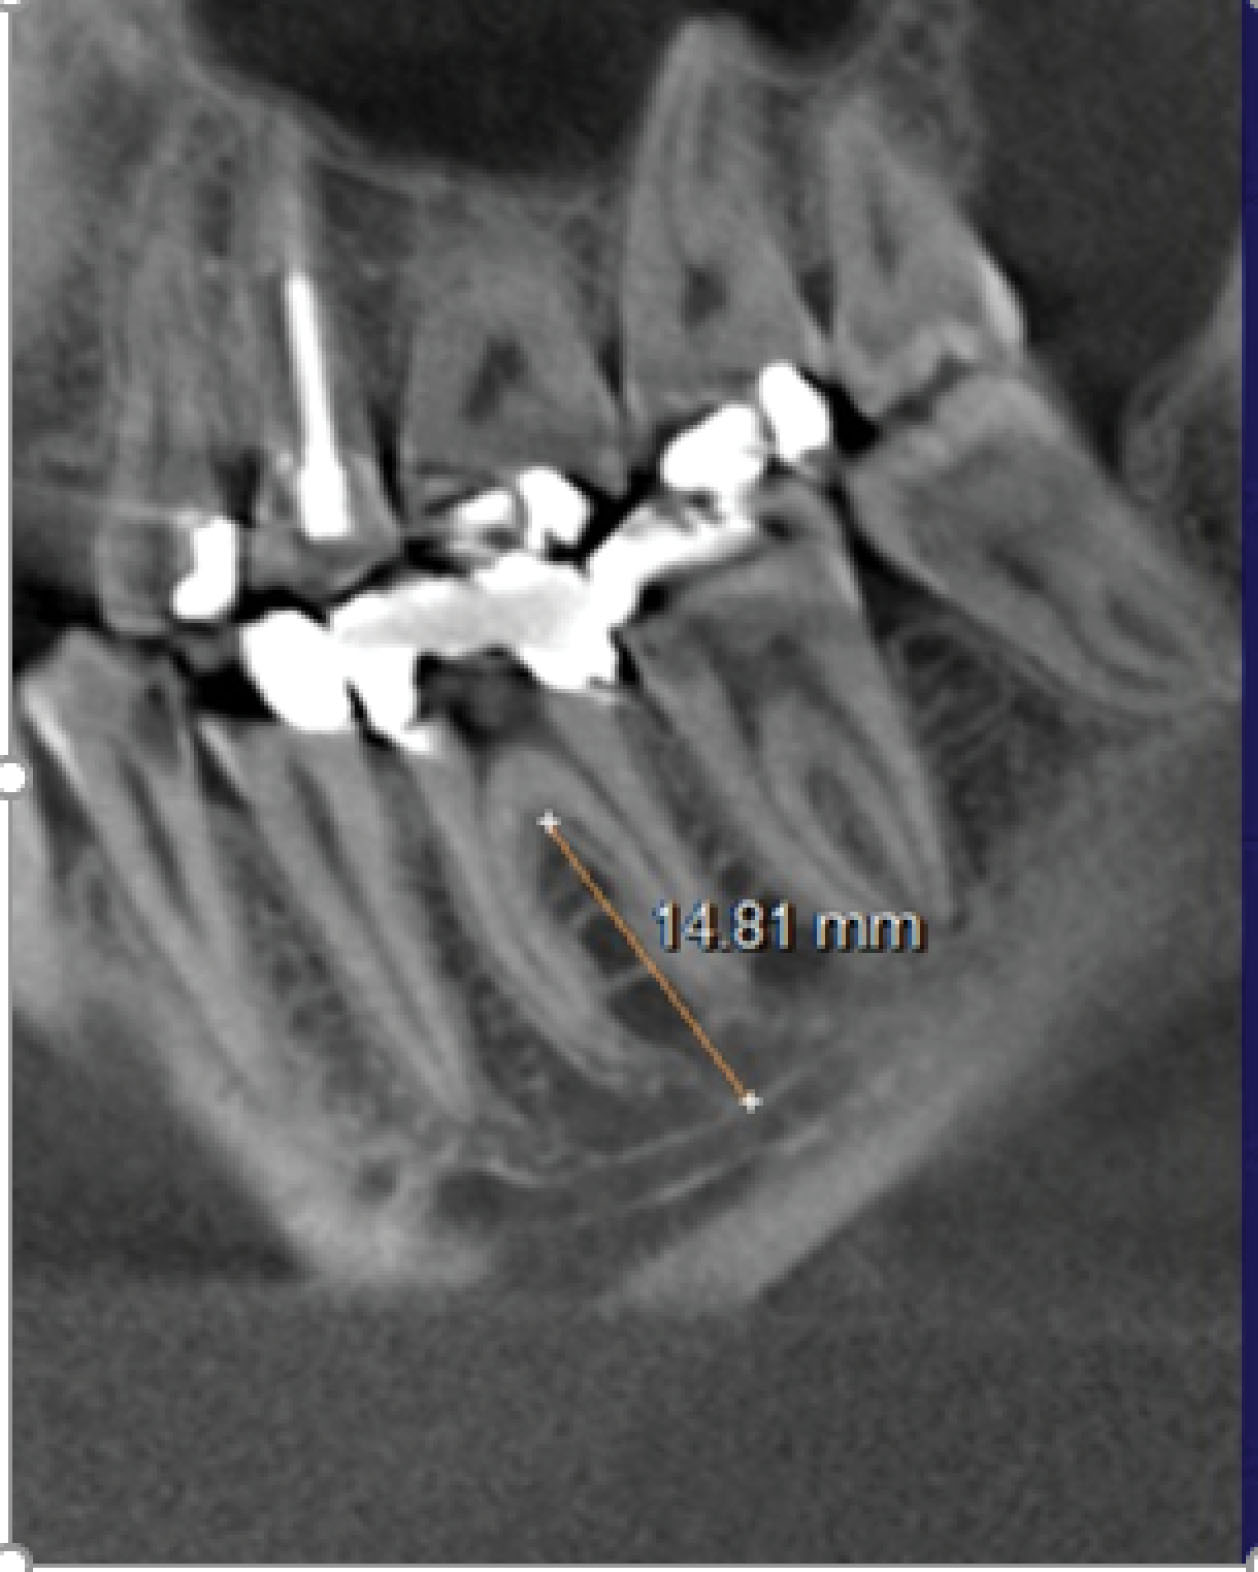

The distance from each molar furcation to the mandibular canal (IAN) (Figure 2).

The distance from furcation to the inferior alveolar canal (IAC) was measured in the middle-most coronal CBCT slice

Figure 6 shows these distances for both mandibular first and second molars. The mean measurements were significantly (P < 0.001) different between the two molar locations (a mean of 14.01 mm for the first vs. 11.04 mm for the second), with a greater risk of perforating the lingual cortical plate at the second molar site.

Distances from molar furcation to the inferior alveolar canal (IAC)

Figure 7 presents these measurements. Similar to the distances from furcation to the deepest level of associated lingual concavities, there were significantly (P < 0.001) different values for the two molars, with the second molars again showing smaller distances to the nerve canal.

CBCT is a valuable imaging technique in oral and maxillofacial surgery as it allows accurate diagnosis and treatment with dental implants using three-dimensional images without the financial burden and radiation exposure of conventional computed tomography (CT) scans. Its limitation is that it does not provide a detailed depiction of soft tissue conditions, which did not affect the current analyses of bony anatomy in the posterior mandible. Of all the risks of using IMIs to restore mandibular first and second molars, penetration of the lingual cortical plate and damage to the IAN are prime concerns (Figure 8). Mandibular second molars are more likely to have lingual undercuts (type “U” jaw anatomy) than first molars.7,8 Lingual perforation is estimated to have an occurrence of 1%‒2% only but can result in life-threatening sublingual hematomas,11 nerve damage, inflammation, and infection.12 The distances from furcation to lingual undercut in the present study were significantly lower at second molar sites (11.04 mm vs. 14.01 mm), giving them a higher risk of lingual plate perforation. For example, if a 12-mm-long IMI were to be placed into the ISB of either molar, there would be a theoretical 42.9% risk of perforation at the second molar site vs. 16.5% at the first molar site. Likewise, there is a greater risk of damaging the IAN when IMIs are placed into inter-septal bone at mandibular second molars (furcation to IAN, 12.97 mm vs. 15.07 mm). However, an even greater risk of damaging the IAN exists when IMIs of inappropriate length are placed into molar root sockets rather than into ISB, the greatest risk being at the distal root of the second molar where the mean distal root apex-to-canal distance is only 3.84 mm, much less than the 6 mm required as a margin for safety.13